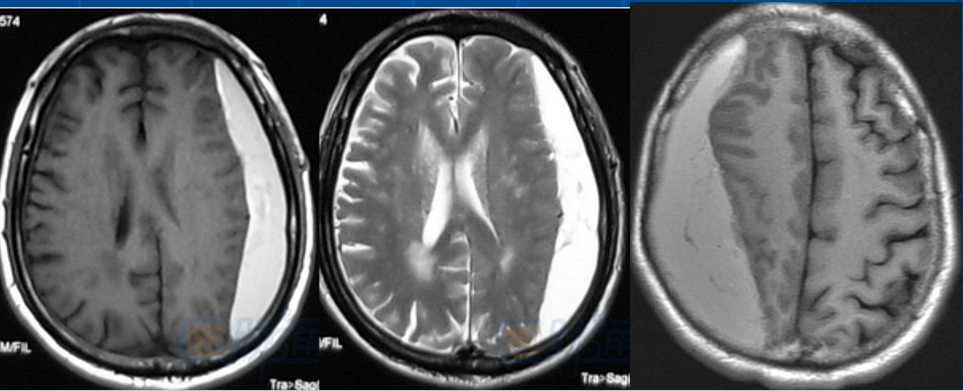

对于有2次以上头部外伤病史导致慢性硬膜下血肿形成者, 或血肿范围较广者, 即使颅脑CT 已经明确诊断, 术前仍有必要再行颅脑MRI检查。

2. 与SDH 疾病本身相关因素,如巨大血肿、双侧血肿、血肿腔内有分隔、血肿机化、CT 表现为高/混杂密度;

血肿分隔多房。

增强MRI扫描对发现高龄脑萎缩、血肿分隔多房、包膜形成、血肿机化等有重要作用。

脑组织顺应性差,血肿机化、包膜。

存在分隔。